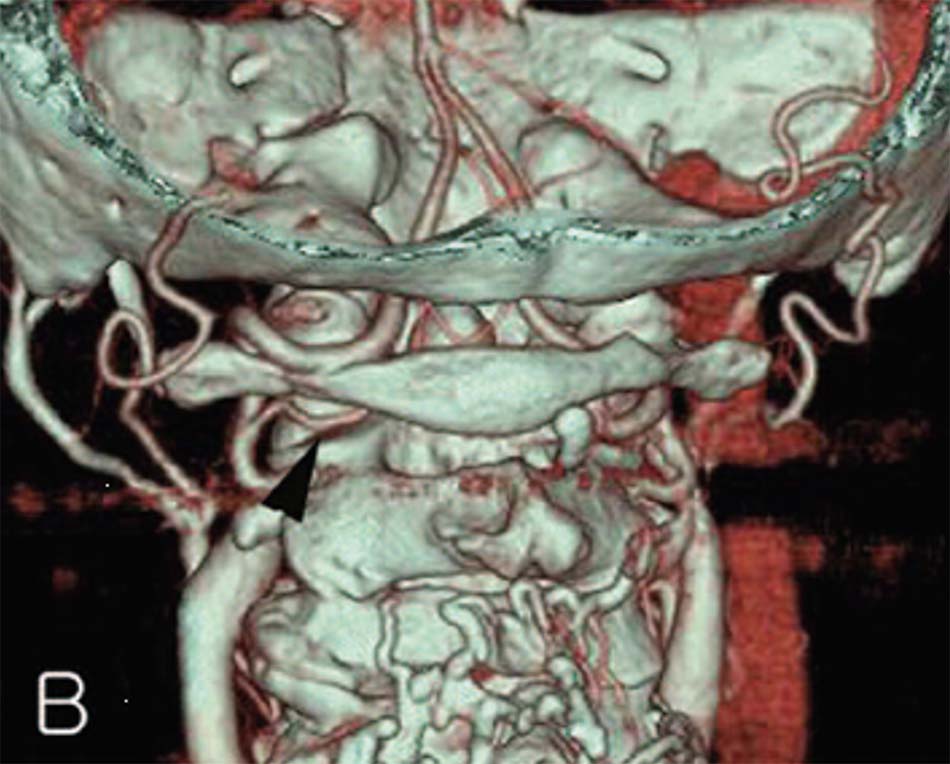

1.4.1. Mối liên quan giữa động mạch đốt sống và cấu trúc C1-C2

- Đoạn V1: Từ lỗ ngang đốt sống C3 đến lỗ ngang đốt sống C2 Sau khi ra khỏi lỗ ngang đốt sống C3, động mạch đi lên trên và ra trước tạo thành rãnh động mạch trong thân đốt sống C2. Khi lên gần tới diện khớp C1 – C2 động mạch đi vòng ra sau (tạo góc trung bình 86 độ) song song với diện khớp C1 – C2 để vào lỗ ngang đốt sống C2. Khoảng các đường giữa thân đốt sống C2 đến động mạch đốt sống trung bình 11,7mm [54].

- Đoạn V2: Từ lỗ ngang đốt sống C2 đến lỗ ngang đốt sống C1 Động mạch đi từ lỗ ngang đốt sống C2 đến lỗ ngang đốt sống C1, đoạn này chủ yếu động mạch liên quan đến hai rễ xuất phát từ hạch thần kinh của C2. Động mạch nằm phía trước của hai rễ thần kinh C2. Khoảng cách từ rễ thần kinh C2 đến động mạch trung bình 8mm [54].

- Đoạn V3: Từ lỗ ngang đốt sống C1 đến lỗ chẩm Sau khi thoát ra khỏi lỗ mỏm ngang đốt sống C1, động mạch đi lên trên và vòng ra sau 1 góc 90 độ tạo một rãnh động mạch ở bờ trên cung sau đốt sống C1 sau đó chui qua lỗ chẩm cùng tuỷ sống đi vào trong não. Rễ thần kinh của C1 nằm sau và dưới so với động mạch đốt sống, chiều dài động mạch đoạn này trung bình 35mm. Khoảng cách từ đường giữa đến rãnh động mạch đốt sống trung bình 22,1mm [54].